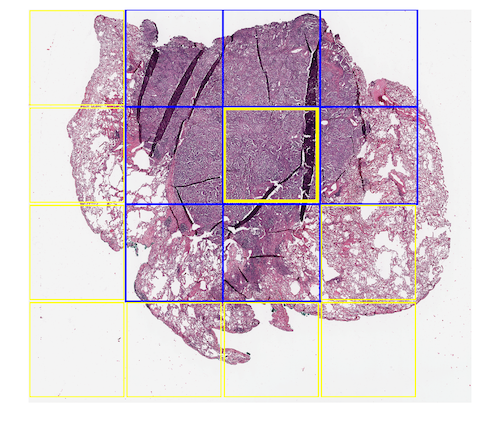

To evaluate the generalization and the practical performance, we also selected five WSIs from the NIH dataset222https://gdc.cancer.gov. We selected WSIs from three different organs (kidney,lung and colon). Figure 3 shows two sample WSIs alongside the boundary boxes of our classifier.

Classifiers, which are trained on small datasets predominantly fail to generalize on new classification categories. In our experiments, we selected five new WSIs with a noticeable amount of folded tissue from the NIH dataset to evaluate the ability of deep features and SVM to generalize to unseen cases. We applied our method in different window sizes with no overlap. All patches will be resized to before feeding to the network. Figure 3 shows sample WSIs from NIH database with different window sizes. Blue boxes are representative of the presence of folded tissue while a yellow box represents normal tissue. The overall accuracy in generalization test set with pixel size dropped to . A possible explanation for this result may be the lack of adequate fold pattern samples in the training set. Besides the difference in an organ type, scanner brand should also be considered. However, as we trained and tested the classifiers for patch-wise tissue detection, one has to bear in mind that the detection of one tissue fold is sufficient to flag a scan for visual inspection.

It can be seen in Figure 3(b) that there is a folded patch which has not been detected. There might be some justifications for this false negative -yellow window in Figure 3 (b)-. The first one is that our training dataset enclosed the entire folded tissue within each patch (i.e., no folded tissue was split between two patches). In this false negative example, however, the patch does not contain all of the folded tissue, and parts of the folded tissue are contained within the neighbouring patches. The same error has occurred in Figure 3(c). The second justification is that the training patch sizes were about 5000 by 5000 pixels, while the experiment window size was 1500 by 1500, therefore training with bigger size patches (patch in lower magnification) might have been the reason for false negatives.